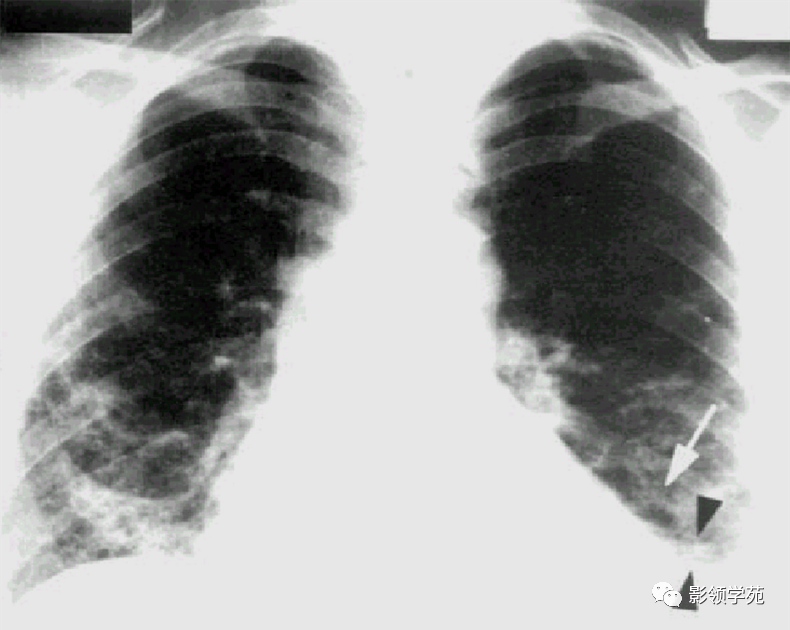

血行转移:双肺多发密度一致、大小形态不一结节状影(下图)

左乳切除术后,左肺下野两个大小不等高密度影。